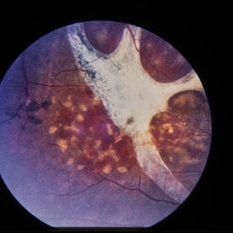

Choroidal rupture with fresh hemorrhage

Condition/keywords: trauma